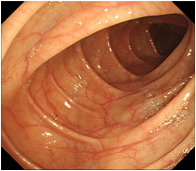

大腸CT(仮想大腸内視鏡)導入

内視鏡を使用せず、検査前に肛門から炭酸ガスを注入し大腸を膨らませた状態でCT撮影(仰向けとうつ伏せ)を行う新しい検査です。得られた画像にコンピューター処理を加え、仮想大腸内視鏡検査として診断を行います。大腸内視鏡検査に比べ比較的、前処置(検査前に大腸内をキレイにする)や検査中の苦痛が少なく、身体に優しい検査です。

大腸CT画像(正常部位) 大腸内視鏡画像(正常部位)